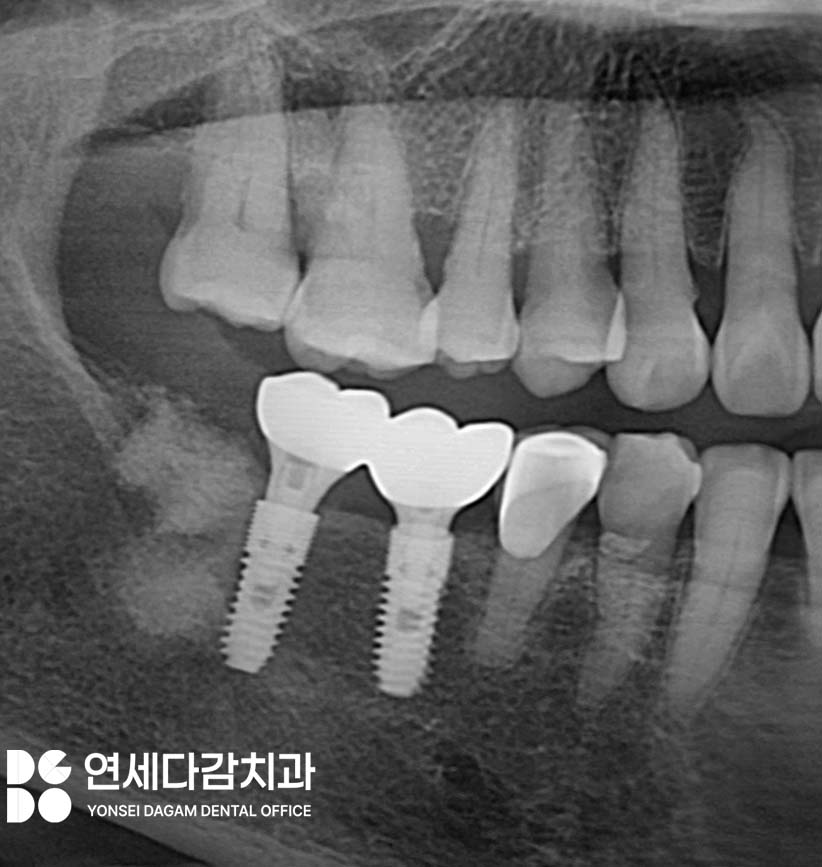

SCRP 타입이란?

Screw Retained Prosthesis의

약자로,

임플란트에 체결되는 보철물을

나사로 고정하는 타입을 말합니다.

현재 널리 사용되고 있는 타입으로

어디서든 임플란트 보철물을

수리할 수 있습니다.

향후 유지관리나 수리가

필요할 때 편의성을 높여줍니다.

어버트먼트(abutment)나 크라운이

나사로 직접 체결되어

탈착할 수 있는 구조여서

보철물 탈부착 용이,

청소와 유지 관리 편리하여

장기적으로 사용하기에 유리합니다.